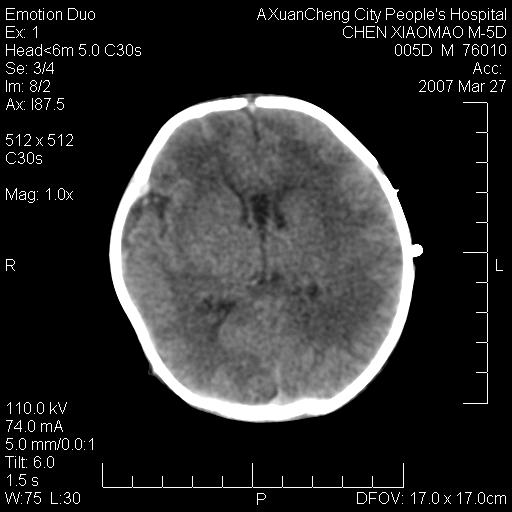

大家看看可有出血?另外枕骨中央是骨缝还是骨折

缝是正常的,但患儿有hie

大家看看可有hie ?还有左侧枕部胡形高密度ct为45~53hu,可有硬膜下血肿?

左颞枕部有出血,枕骨有骨折

枕骨骨折可以下,应该比较明显,颅内还是正常的,不放心的话,短期随访。

未见明显异常,,那是横窦影,“缝”是后囟